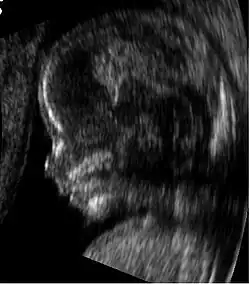

Medical imaging in pregnancy may be indicated because of pregnancy complications, intercurrent diseases or routine prenatal care.